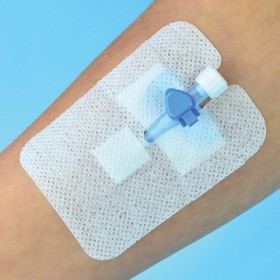

3M NASOGASTRISCH FIXATIEAPPARAAT 3M Code: 1500NG Neusmaagapparaat 4,5x4,7 cm - klein Minimale bestelling: verpakking. vanaf 50 Het 3M Nasogastric Fixation Device zorgt voor een veilige fixatie van voedingssondes en andere sondes waarmee therapie via de neus wordt toegediend. Dit fixatie-apparaat voor een neusmaagsonde is een gebruiksvriendelijke oplossing die helpt om doorligwonden te voorkomen en het risico op huidletsel door medische kleefstoffen (MARSI) te minimaliseren. - stevigere pasvorm: ...

3M NASOGASTRISCH FIXATIEAPPARAAT 3M Code: 1500NG Neusmaagapparaat 4,5x4,7 cm - klein Minimale bestelling: verpakking. vanaf 50 Het 3M Nasogastric Fixation Device zorgt voor een veilige fixatie van voedingssondes en andere sondes waarmee therapie via de neus wordt toegediend. Dit fixatie-apparaat voor een neusmaagsonde is een gebruiksvriendelijke oplossing die helpt om doorligwonden te voorkomen en het risico op huidletsel door medische kleefstoffen (MARSI) te minimaliseren. - stevigere pasvorm: de kleefstof blijft tot 48 uur op zijn plaats in moeilijke posities - huidvriendelijk: vermindert het risico op doorligwonden doordat de neus-maagsonde vrij kan hangen - huidvriendelijk: biedt de vereiste fixerende werking en minimaliseert tegelijkertijd huidbeschadiging - gebruiksgemak: eenvoudig aan te brengen en te verwijderen, waardoor de aanbrengtechniek kan worden gestandaardiseerd - transparantie: zorgt voor zichtbaarheid van de huid, neussondes en andere sondes, wat de beoordeling vergemakkelijkt - niet-klevende lip aan het uiteinde van de staart vergemakkelijkt het verwijderen